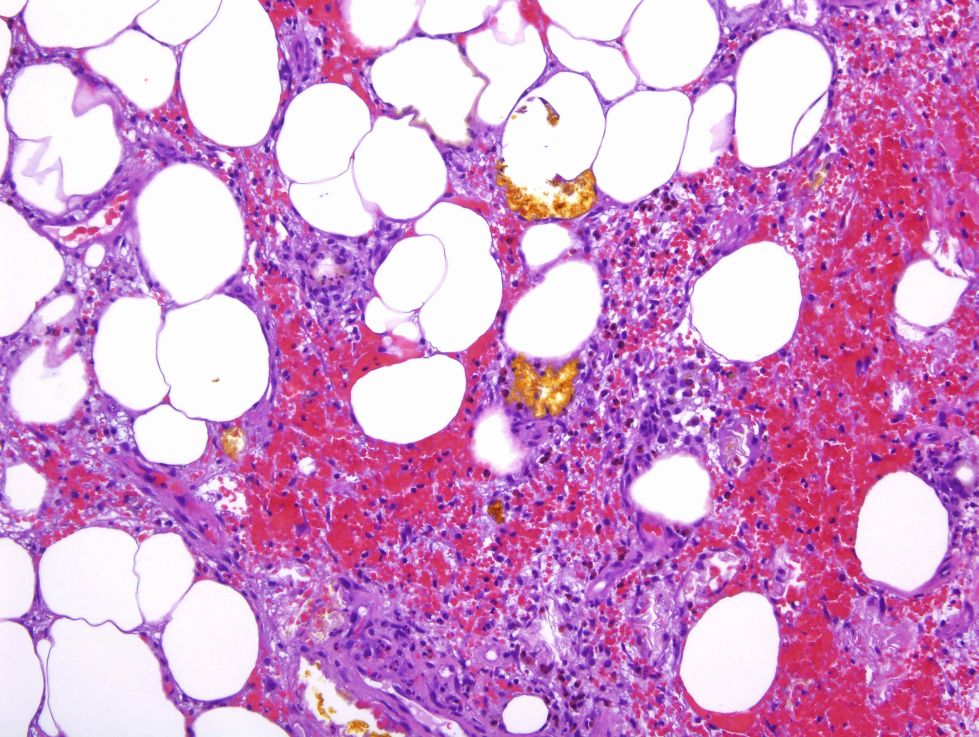

Cas dermatopatologia. Un cas adequat per a aquesta estació de l'any

Gener 2013

Podria suggerir-se el diagnòstic sense conèixer l'historial clínic?